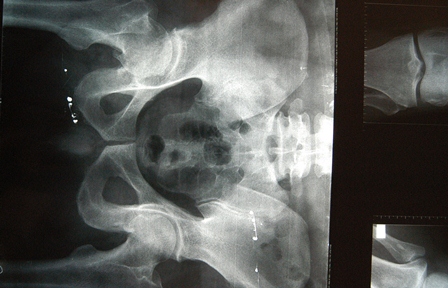

Añadió que aunque puede presentarse en cualquier hueso, la fractura de cadera es la más peligrosa, por ser altamente discapacitante e incluso puede llevar a la muerte, ya que cuatro de cada 10 personas que la sufren, no rebasan el siguiente año de vida a causa de diversas complicaciones como infecciones pulmonares, trombosis y formación de ulceras, por la poca o nula movilidad de quienes quedan postrados en una cama o limitados a una silla de ruedas.

Torres Martínez señaló que al año se presentan alrededor de 21 mil casos de fractura de cadera y que la importancia de atender esta enfermedad lo antes posible, radica en que la población mexicana tiende al envejecimiento.

En la actualidad se estima que hay 20 millones de personas por arriba de los 50 años de edad; para 2050 se prevé que esta cifra llegue a 55 millones, por lo que los casos de fractura de cadera podrían incrementarse hasta 110 mil al año, explicó.